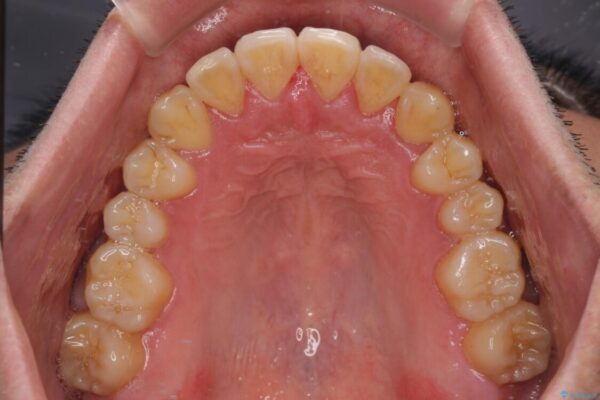

治療前

• 八重歯とクロスバイト 目立たないワイヤー装置で矯正治療 治療前画像